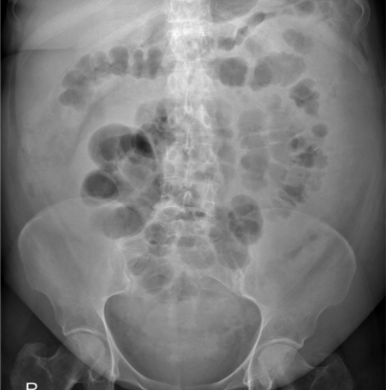

Patient with severe abdominal pain. What does the image show?

What is the likely pathology?

Thumbprinting

Inflammation of the bowel wall leads to thickening of the haustral folds. This results in the radiological sign of thumbprinting, a characteristic finding in patients with active ulcerative colitis.